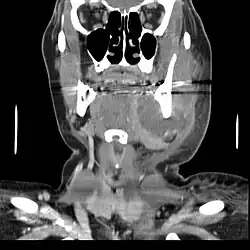

Schreitet die odontogene Entzündung fort, kann sich aus der Osteomyelitis ein Abszess bilden, eine umkapselte Eiteransammlung, die durch entzündliche Gewebseinschmelzung entsteht. Durch den entstehenden Druck sucht sich der Pus (Eiter) einen Entlastungsweg nach außen. Daraus entsteht wiederum zunächst eine schmerzhafte Spannung des relativ widerstandsfähigen Periosts, bevor der Eiter durch das Periost und das umgebende Weichgewebe fistelnd durchbricht.

Daraus kann sich die eitrige odontogene Entzündung phlegmonös, etwa mit Entstehung einer Mundbodenphlegmone, fortentwickeln, die sich bei einer Ausbreitung nach cranial zu einer Meningitis oder einem Hirnabszess entwickeln kann, die beide lebensbedrohlich werden können. Aus einer periapikalen Ostitis oder einer parodontalen Infektion an oberen Molaren kann sich eine odontogene Sinusitis (Kieferhöhlenentzündung) entwickeln, die etwa 20 % aller Sinusitiden ausmacht. Dabei bricht das entzündliche Exsudat bei einer Sinusitis maxillaris (das Mittelgesicht und den Unterkiefer betreffend) durch den Kieferhöhlenboden in die Kieferhöhle durch. Von dort aus kann sich die Entzündung in weitere Nasennebenhöhlen (Stirnhöhlen, Siebbeinzellen, Keilbeinhöhle) ausbreiten.